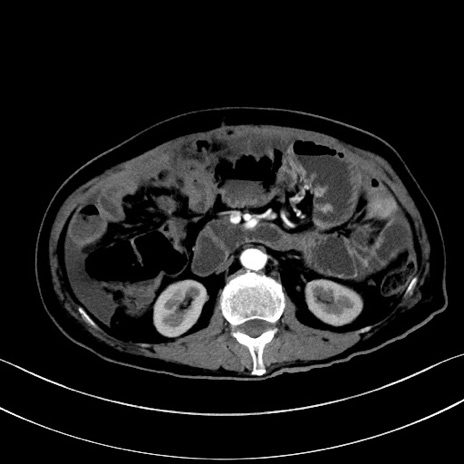

症例28(横断像)

【症例】60歳代男性

【主訴】嘔吐

【現病歴】胃癌にて胃全摘後。食思不振が悪化し、夜中に嘔吐することがある。

【既往歴】胃癌、胃全摘、脾摘、胆摘後

【データ】WBC 5900、CRP 10.56